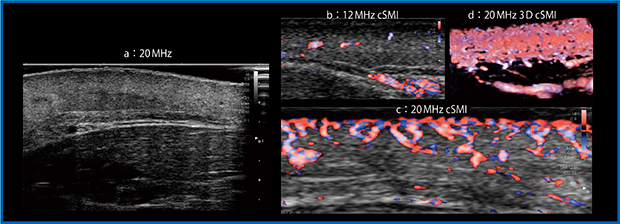

図17は丹毒である。iDMS PLI-2004BXはきわめて高分解能なため,1つ1つのピクセルが明瞭で,膿瘍の部分に血液の流動性があることがはっきりとわかる(図17 a)。本症例には強い炎症があるが,12MHzプローブのcSMIでは膿瘍も不明瞭で,表皮や真皮あたりで増加しているはずの血流も描出されていない(図17 b)。しかし,iDMS PLI-2004BXのcSMIでは,プローブ直下の領域にて非常に強い炎症による血流の増加が一目瞭然であり(図17 c),血流が遅いほどわずかな位相差を検出する必要があり,高周波が有利に働くことが理解できる。さらに,iDMS PLI-2004BXのcSMIを3D表示すると,これまでダイナミックな画像での観察が不可能だった,皮膚直下で血管が絨毯のようになっている現象も観察可能である(図17 d)。iDMS PLI-2004BXは非常に大きなポテンシャルを有しており,使い方次第で優れた威力を発揮すると思われる。

図17 丹毒における12MHzプローブ(b)とiDMS PLI-2004BX(20MHz)(a,c,d)の比較